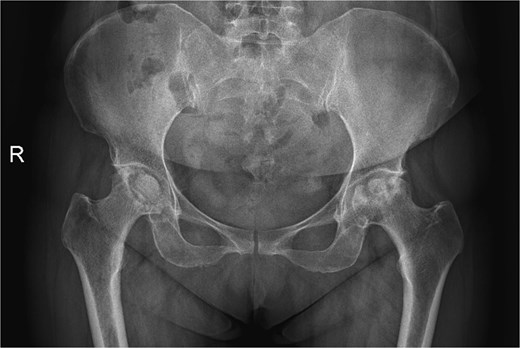

A 47-year-old woman, weighing 65 kg with a height of 158 cm and a body mass index (BMI) of 26 kg/m2, came to our hospital with chief complaints of bilateral hip pain and difficulty walking for 1 year and underwent left THA and 1 week of right THA because of bilateral avascular necrosis and collapse. X-ray of the pelvis of both hips revealed bilateral avascular necrosis and collapse (Fig. 1). A posterolateral approach was used for the bilateral hips in the lateral decubitus position. The implant consists of a Pinnacle cup (DePuy), DELTA ceramic liner and ceramic femoral head (BIOLOX DELTA), and collarless Corail stem (DePuy). After fixation of the acetabular cup, the senior surgeon placed the ceramic liner into the metal shell by hand. Unfortunately, the liner was not placed in the centre position and became stuck. The edge of the tilted ceramic is slightly greater than the cup, perhaps only 5 mm or less. The surgeon attempted to remove the liner by tamping the edge with the plastic impactor using light force several times, but the process of doing so fractured the ceramic liner (Fig. 2). The alumina ceramic fragment of the liner was removed carefully (Fig. 3), and the site was irrigated well. A 32-mm polyethylene liner and a ceramic femoral head were implanted. Full weight-bearing was allowed on postoperative day 1 with a walking aid. The patient remained hospitalized for 8 days to monitor closely for early perioperative complications. Sutures were removed on the seventh day, and the laboratory results indicated an absence of infection. At the 2-month postoperative interval, the patient achieved a successful outcome, with complete resolution of her preoperative symptoms as well as a return to all her activities of daily living (Fig. 4).

A radiograph was obtained preoperatively of a 47-year-old woman with bilateral avascular necrosis and collapse.